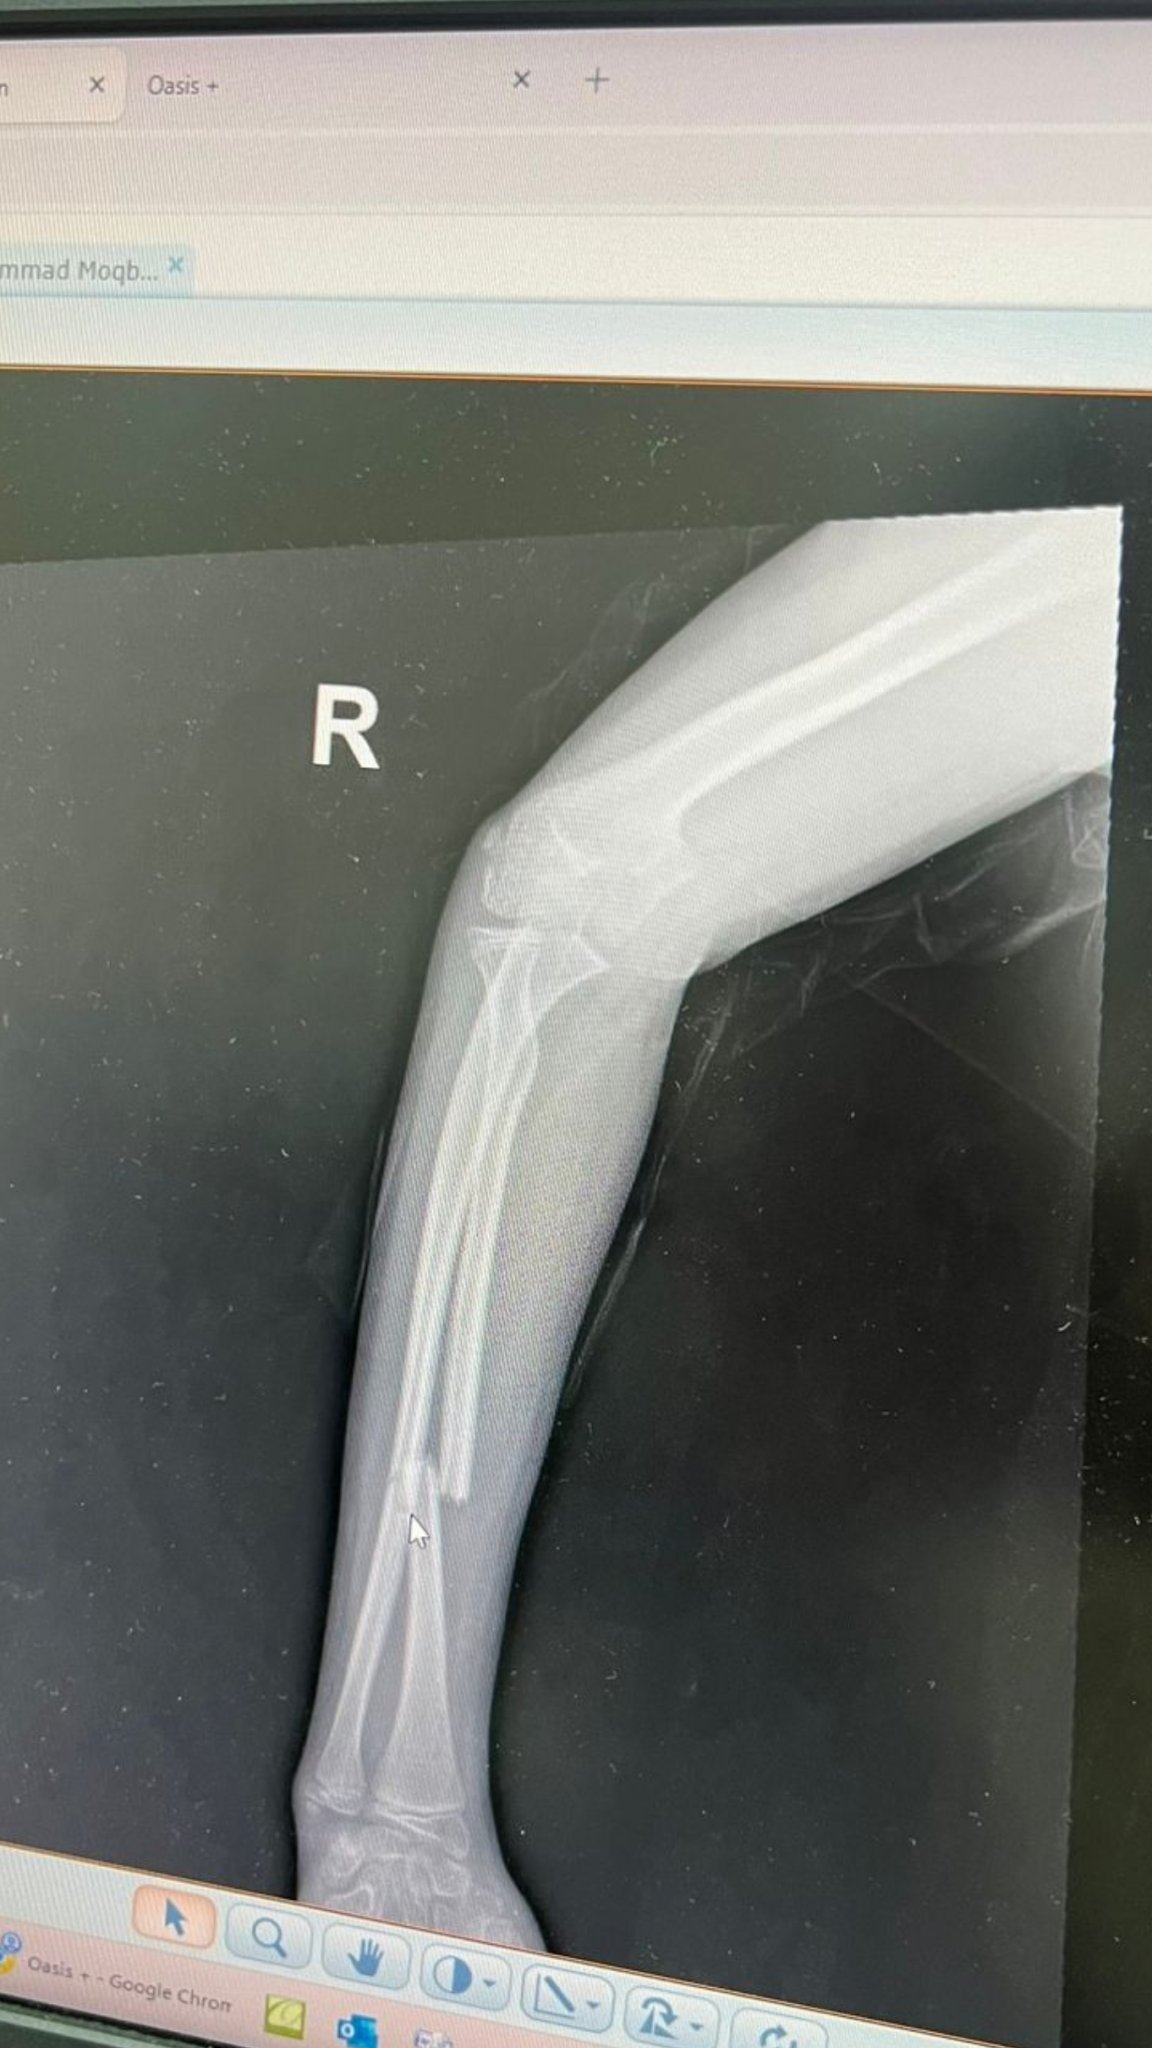

طفل زائر من دولة عربية، يبلغ من العمر 13 عاماً، تعرّض لحادثة سقوط يوم الجمعة 15 شوال 1447هـ نتج عنه كسر متزحزح في عظّمتي الساعد الأيمن.

تستوجب حالته تدخلًا جراحيًا عاجلًا لتثبيت الكسر، ولتلافي حصول مضاعفات أو إعاقة دائمة - لا سمح الله -.